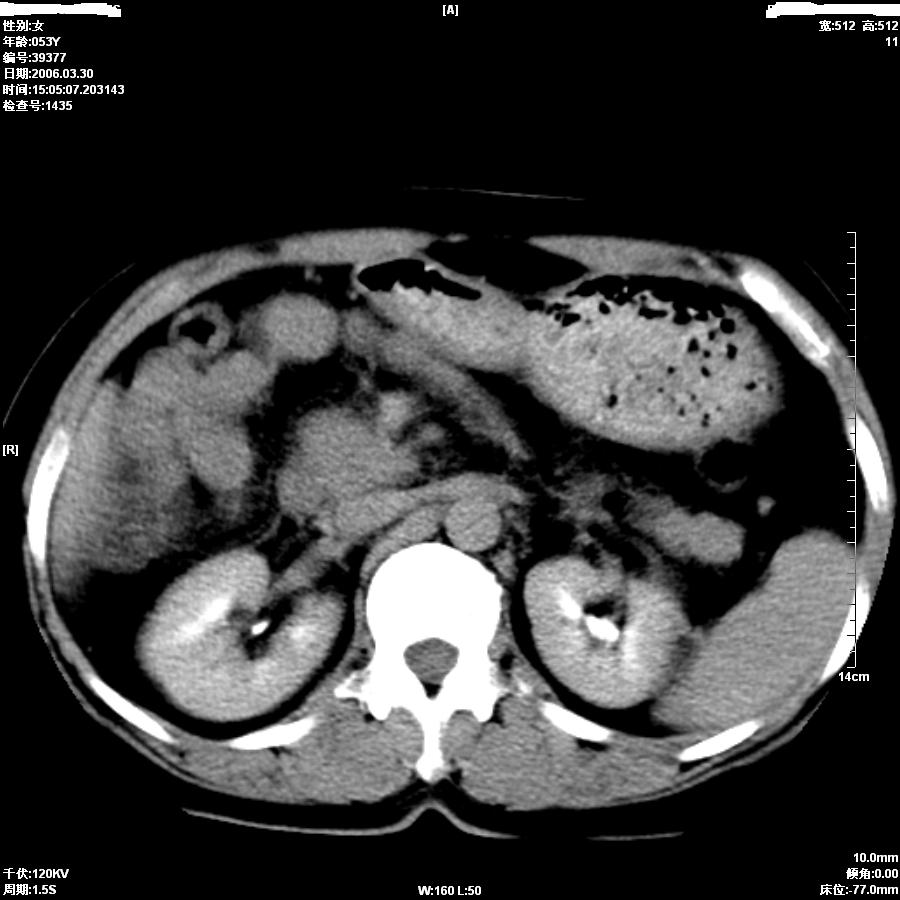

女,50岁,上腹部憋胀,疼痛月余。做增强刚打了50ml造影剂病人就出现了较重的过敏,所以强化不成功。

平扫第8图胆总管内似见结石,上部胆道扩张,肝内片影无强化,胆囊不清,胃小弯壁略厚。

从平扫:肝脏肿块,胰头周围结构不清似有结节。考虑恶性肿瘤(首先要排外肝胆感染病变)。胆管癌>肝癌。建议mri。

不知本病人有没有作过胆囊切除手术?

如果胆囊未切除,首先考虑胆囊癌肝侵犯。

中老年妇女,肝门、胆囊区病变,病变实体形态欠清楚,胆囊癌可能性极大。

鉴别诊断:肝癌;胆管癌;

理由:1、低密度病灶,动脉期末有一点强化。

2、左肝内胆管扩张。

3、肝门区胆管壁静脉期有强化。

疑问:第六副图片胃小弯局部胃壁增厚吗?知情者请解答!!